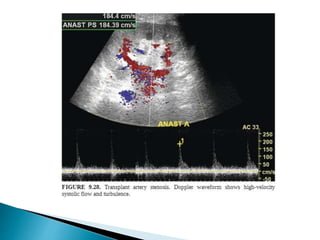

 2.Renal artery stenosis.

 Mc vascular complication

 reduced renal function; htn; a bruit.

 @ host artery proximal to anastomosis related to

atherosclerosis or trauma at time of surgery.

 @ anastomotic site  Surgical technique , suture material ,

perfusion injury of vessels.

 Post anastomotic site :- refection , abnormal local

hemodynamics , extrinsic compression.

 Require arterial imaging for accurate complication either with

USG doppler , CTA/MRA.

 Percutaneous Transluminal angioplasty is the preferred mode of

treatment